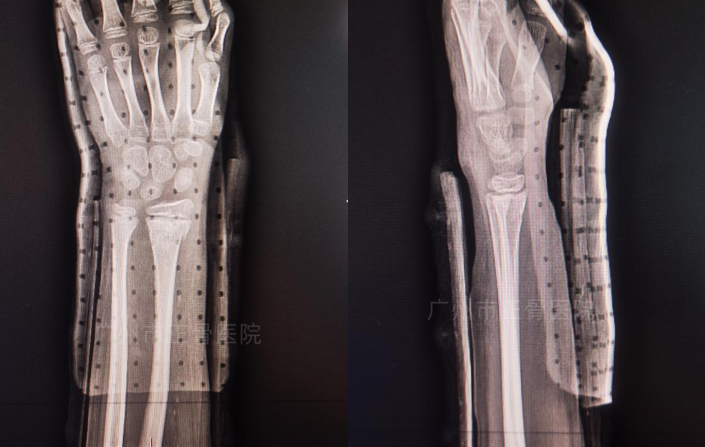

X线片结果示:“左桡尺骨远端骨折,均稍向内后方成角,桡骨远端向外前上方移位,尺骨骨折端对线好,下桡尺关节脱位,骨骺板损伤。”

▲复位前,骨折移位明显